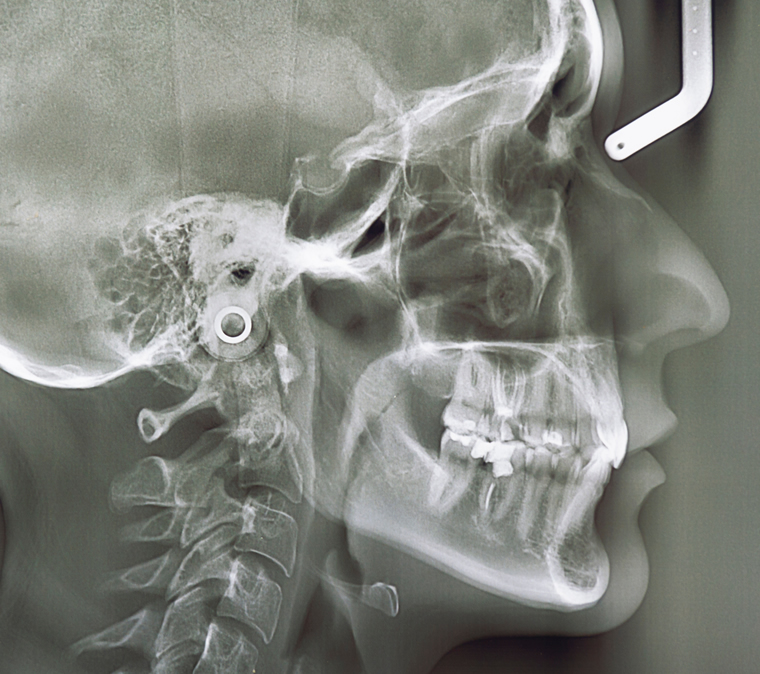

矯正専門医による顎関節、

かみ合わせにもこだわった

機能美マウスピース矯正

矯正治療を始めるうえで、最も大切なことは治療前の分析と診断です。

この治療前の診査・診断によって

キレイな歯並びになるか?

より正しい噛み合わせになるか?

などを入念に分析した上で治療計画を立てます。

ただし、マウスピース矯正は、矯正治療前の診査・診断、治療計画がとても重要になります。この診査・診断、治療計画を誤ると仕上がりに大きな影響を与えてしまいます。

当医院では、ただ歯並びをキレイに整えるだけでなく、顎関節やかみ合わせにも配慮した診査・診断を行い、綿密な治療計画を立てていますので、ぜひご安心してお気軽にご相談ください。

ただキレイに並べるだけでなく、顎関節、かみ合わせにもこだわったマウスピース矯正が当医院の特徴です。